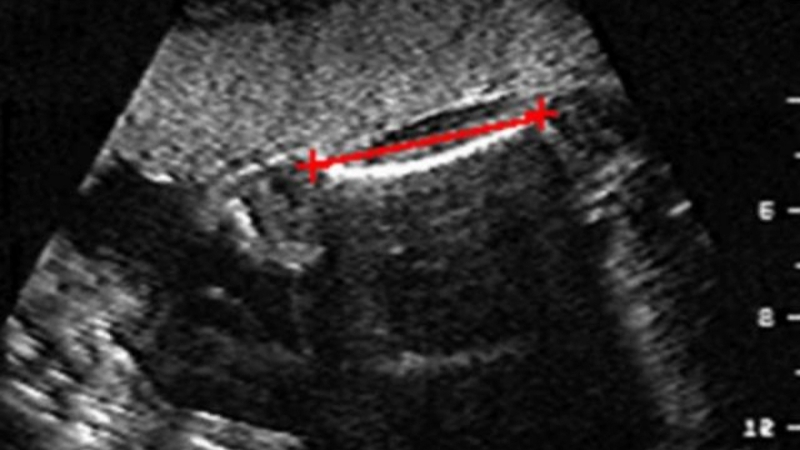

Chiều dài xương đùi của thai nhi

Một cách khác để dự đoán giới tính thai nhi theo kinh nghiệm dân gian là dựa vào chiều dài xương đùi thai nhi và đường kính đỉnh đôi. Bạn chỉ cần lấy đường kính đỉnh đôi nhân hai, sau đó trừ đi chiều dài xương đùi của bé. Nếu kết quả nhỏ hơn 21 là con trai, ngược lại là con gái.

nhìn hình siêu âm làm sao biết trai hay gái Dự đoán giới tính thai nhi dựa vào chiều dài xương đùi và đường kính đỉnh đôi